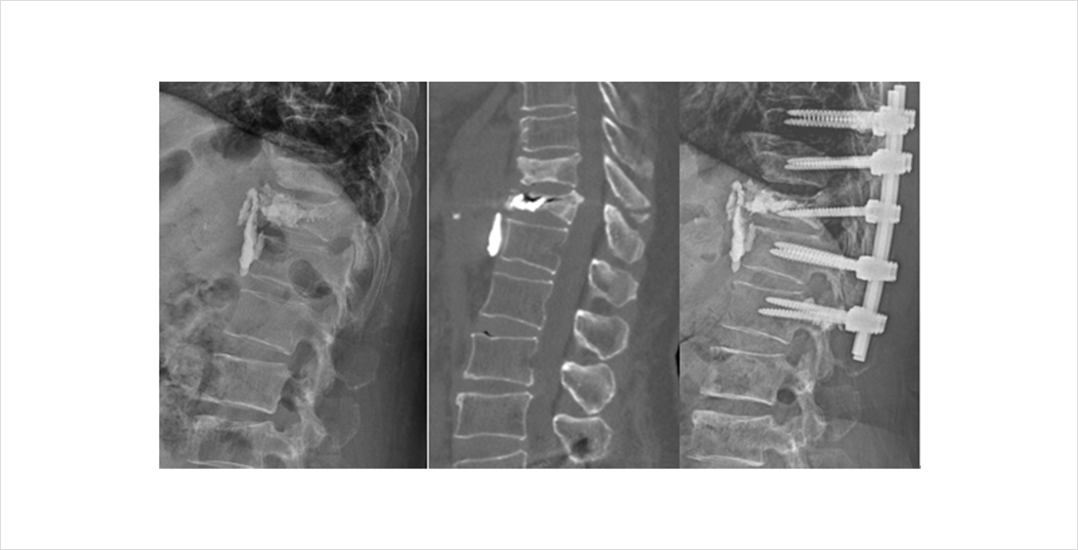

척추 골절이 심하여 골편이 신경을 압박하거나 골유합이 되지 않아 지속적인 불안정증이 있는 경우 척추체 고정술을 필요할 수 있습니다. 척추체 고정술이 필요한 경우에는 전문의와 자세한 상담이 필요합니다.

척추체 성형술을 시행하였지만 골시멘트와 유합이 일어나지 않고 척추체 내부에 괴사가 일어나면서 척추체의 붕괴가 진행되고 이로 인한 통증이 지속되는 경우도 있습니다. 이러한 경우에는 척추 불안정과 지속되는 통증을 해결하기 위해 척추체 고정술이 필요할 수 있습니다.